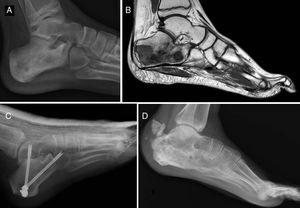

Del total de sarcomas, 32 (78,05%) correspondieron a Ewing de tipo óseo y los 9 restantes (21,95%) a Ewing extraesquelético. Las localizaciones del grupo óseo se repartieron entre: fémur (10 casos, 31,25%), columna (8 casos, 25%), peroné (4 casos, 12,5%), pelvis (3 casos, 9,38%), calcáneo (2 casos, 6,25% figura 2), tibia (2 casos, 6,25%), húmero (2 casos, 6,25%) y 5.° metatarsiano (1 caso, 3,13%). Uno de los pacientes del grupo óseo debutó con una fractura patológica a nivel diafisario femoral, y otro paciente sufrió otra fractura patológica también femoral durante los primeros ciclos de quimioterapia neoadyuvante. En lo que al grupo extraesquelético se refiere, los emplazamientos fueron: muslo (3 casos, 33,33%), pierna (2 casos, 22,22%), hueco poplíteo (2 casos, 22,22%), paravertebral (1 caso, 11,11%) y epidural (1 caso, 11,11%). En la tabla 1 se expone un resumen demográfico de la serie de pacientes.

Sarcoma de Ewing de calcáneo, imágenes de radiología convencional (A) y de RM (B). Fue tratado mediante resección y reconstrucción con aloinjerto (C). Radiografía tras 6 años de evolución (D) en la que se aprecia artrodesis consolidada calcáneo-astragalina y calcáneo-cuboidea y fractura-avulsión de tuberosidad posterior ocurrida en el primer año tratada de manera conservadora porque no generó alteración funcional.